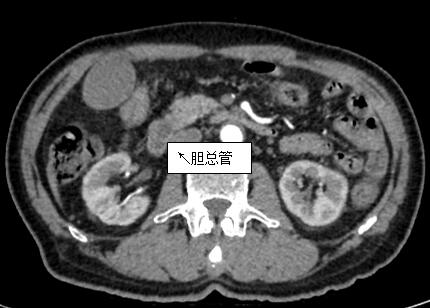

69歲王姓患者,因“發(fā)現(xiàn)無痛性黃疸1月”入院,根據(jù)患者病史,患者診斷傾向于壺腹部腫瘤所致梗阻性黃疸。予以完善腹部CT及上腹部MRI加MRCP均顯示肝內外膽管擴張,未發(fā)現(xiàn)明顯膽管,胰腺及十二指腸乳頭部腫瘤,且患者CA199正常。以前醫(yī)院未引進超聲內鏡,這類患者到此就遇到診斷瓶頸。此患者經過消化內科張丹霞副主任醫(yī)師完善超聲內鏡檢查后,可以清楚顯示膽總管下段壁內軟組織占位?;颊咄ㄟ^超聲內鏡檢查診斷明確,轉至肝膽外科行手術治療。

上腹部CT圖片